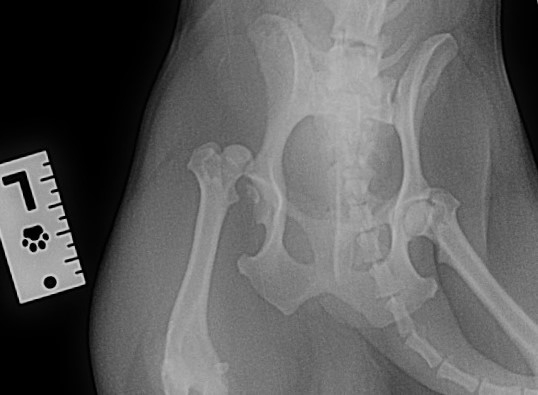

Боря – так назвали его в прошлой жизни…он попал под машину, а потом его решили вывезти по дальше к ЖД путям, чтобы не заниматься им. В чем его вина?! Не понятно! Малыш не наступает на одну лапу, плачет, сделали повторный рентген – головка бедра смещена и все-таки требуется срочная дорогостоящая операция.